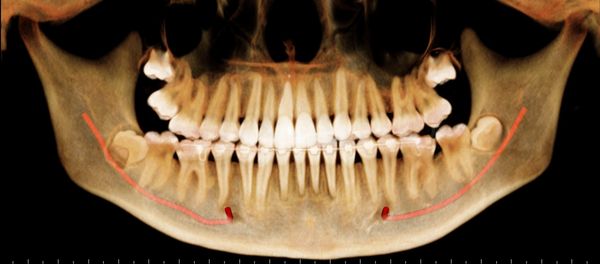

Multiple Mental Foramina - important for surgeries planned in the region, either for dental implants, impacted teeth or periodontal issues

CBCT derived Grey-scale Panoramic view (OPG) of the Jaws

CBCT derived Panoramic view (OPG) of the Jaws

CBCT derived Osseous Panoramic view (OPG) of the Jaws